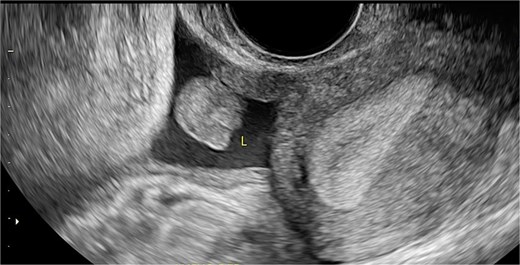

Stage III pelvic inflammatory disease (PID) was suspected based on ultrasound (Figs 1–3) and gynecological examination, which revealed mild bulging of the right lateral fornix, cervical motion tenderness, and a white, non-foul-smelling vaginal discharge. Empiric intravenous antibiotic therapy was initiated, followed by exploratory laparotomy via a Pfannenstiel incision. Intraoperative findings included an 8 × 5 cm uterus, edematous fallopian tubes, and a simple 5 × 5 cm left adnexal cyst. Cystectomy was performed.

Sagittal transvaginal ultrasound showing free fluid in the uterine fundus.

Transverse transvaginal ultrasound demonstrating a 4.7 cm bilocular cyst in the left ovary and a dominant follicle in the right ovary, with moderate periovarian fluid adjacent to the right ovary.

Transpelvic ultrasound reveals a heterogeneous mass adjacent to the right adnexa measuring 4.6 × 8.4 cm, predominantly hypoechoic with anechoic areas.